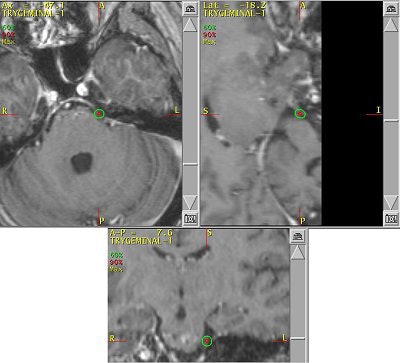

![]() |

| Proper alignment of patient and assembly is confirmed using lasers. Images courtesy of Dr. Kevin Murphy and University of California, San Diego, department of radiation oncology. |